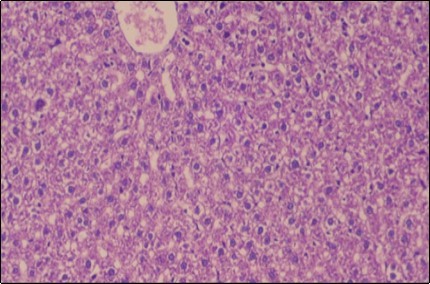

Effect of Ator, Fennel and Their Combination on the Liver of Obese Rats

The histological examination of the livers of control rats feeding standard diet showed normal architecture hepatocytes, blood sinusoid and central vein, figure 6. The rats which were fed on a (HFD), showed swollen hepatocytes with vacuolated cytoplasm filled with fatty infiltration, congested central vein and disappearance of blood sinusoids, figure 7. By comparison, the liver of rats that were treated by fennel after obesity and control mice observed nearly normal of the hepatocytes with eosinophilic cytoplasm, central vein and clear blood sinusoids and more bi-nucleated cells, figure 8. While examination of rats' liver that were treated by Ator and after the obesity appears, they showed mild fatty change in hepatocytes, few hepatocytes retain is eosinophilic cytoplasm and central vein figure 9. Liver of rats that were treated by fennel and Ator after obesity and control rats are showing nearly normal hepatocytes figure 10.

Figure 6.Photomicrogragh of liver section of control rat showing normal architecture Hepatocytes, blood sinusoid and central vein, (H&E) (40X).

Figure 7.Photomicrograph of liver section of obese rat showing swollen hepatocytes with vacuolated cytoplasm filled with fatty infiltration, congested central vein and disappearance of blood sinusoids, (H&E) (40X).

Figure 8.Photomicrograph of liver section of treated rat with fennel herb showing nearly normal of the hepatocytes with eosinophilic cytoplasm, central vein (CV) and clear blood sinusoids and more bi-nucleated cells , (H&E) (40X).

Figure 9.Photomicrogragh of liver section of treated rat with Ator drug showing mild fatty change in hepatocytes, few hepatocytes retain is eosinophilic cytoplasm and central vein , (H&E) (40X).

Figure 10.Photomicrograph of liver section of treated rat both with both fennel herb and Ator drug showing nearly normal hepatocytes (H&E) (40X).